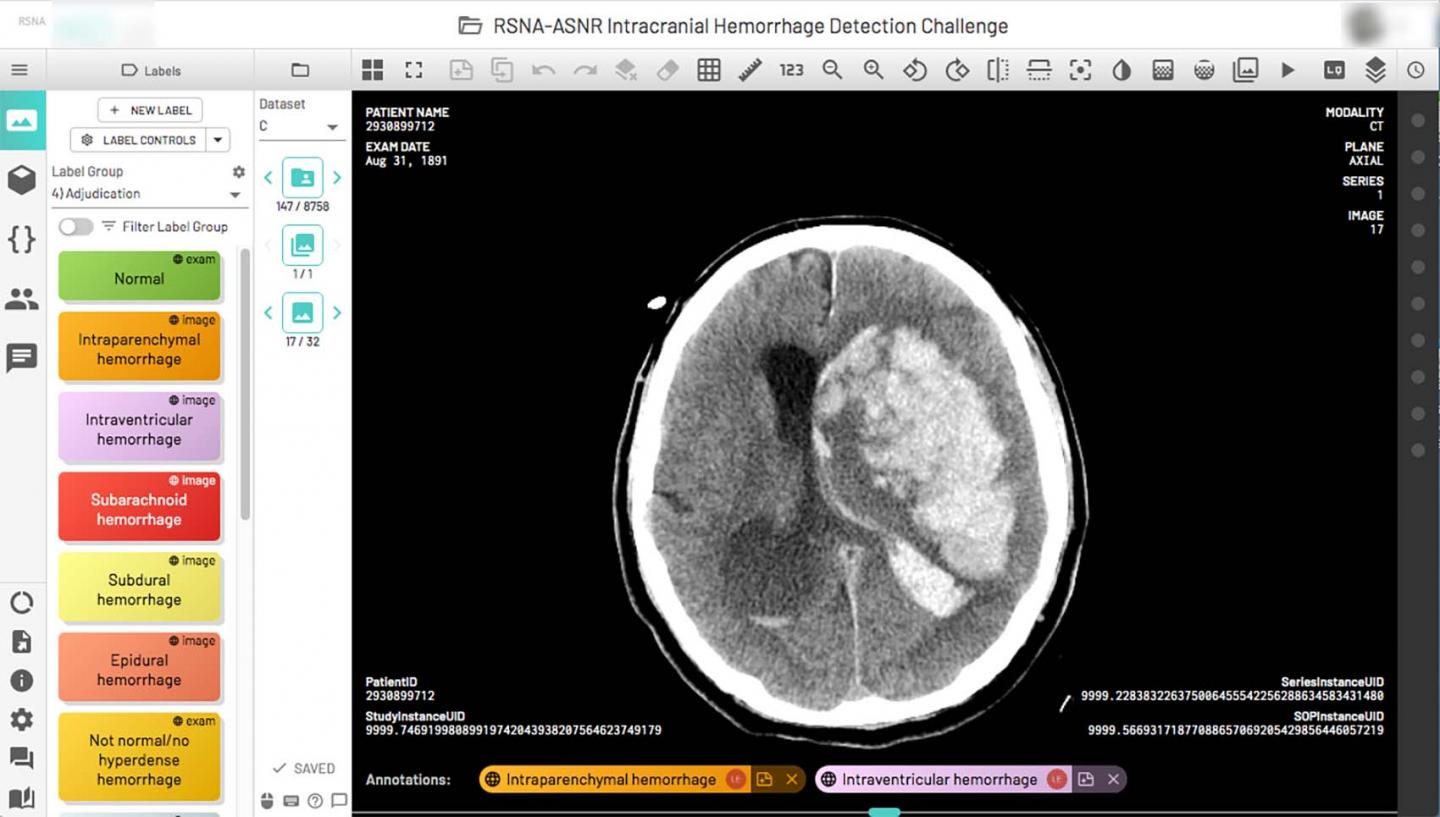

image: A complex multicompartmental cerebral hemorrhage on a single axial CT image displayed using the annotation tool in a single portal window. Hemorrhage labels (left column) relevant to the image display on the bottom of the image once selected. ASNR = American Society of Neuroradiology RSNA = Radiological Society of North America.

RSNA and the American Society of Neuroradiology (ASNR) collaborated to curate the dataset and organizers issued an open call for volunteers within the ASNR membership to annotate the images. A day-and-a-half later, they had 140 volunteers from which they selected 60 to annotate a vast trove of 874,035 brain hemorrhage CT images in 25,312 unique exams. The volunteers marked each image as normal or abnormal. For the abnormal images, they indicated the hemorrhage subtype.